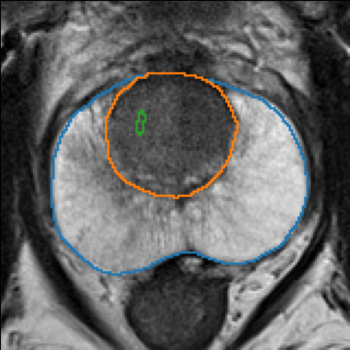

The emergence of multi-parametric magnetic resonance imaging (mpMRI) has had a profound impact on the diagnosis of prostate cancers (PCa), which is the most prevalent malignancy in males in the western world, enabling a better selection of patients for confirmation biopsy. However, analyzing these images is complex even for experts, hence opening an opportunity for computer-aided diagnosis systems to seize. This paper proposes a fully automatic system based on Deep Learning that takes a prostate mpMRI from a PCa-suspect patient and, by leveraging the Retina U-Net detection framework, locates PCa lesions, segments them, and predicts their most likely Gleason grade group (GGG). It uses 490 mpMRIs for training/validation, and 75 patients for testing from two different datasets: ProstateX and IVO (Valencia Oncology Institute Foundation). In the test set, it achieves an excellent lesion-level AUC/sensitivity/specificity for the GGG$\geq$2 significance criterion of 0.96/1.00/0.79 for the ProstateX dataset, and 0.95/1.00/0.80 for the IVO dataset. Evaluated at a patient level, the results are 0.87/1.00/0.375 in ProstateX, and 0.91/1.00/0.762 in IVO. Furthermore, on the online ProstateX grand challenge, the model obtained an AUC of 0.85 (0.87 when trained only on the ProstateX data, tying up with the original winner of the challenge). For expert comparison, IVO radiologist's PI-RADS 4 sensitivity/specificity were 0.88/0.56 at a lesion level, and 0.85/0.58 at a patient level. Additional subsystems for automatic prostate zonal segmentation and mpMRI non-rigid sequence registration were also employed to produce the final fully automated system. The code for the ProstateX-trained system has been made openly available at https://github.com/OscarPellicer/prostate_lesion_detection. We hope that this will represent a landmark for future research to use, compare and improve upon.